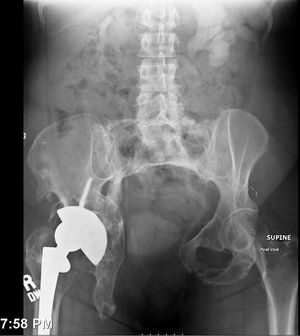

Clinical History: A 45 year old African-American nulligravida female presented to the emergency department complaining of 8/10 nonradiating pain deep within her vagina.